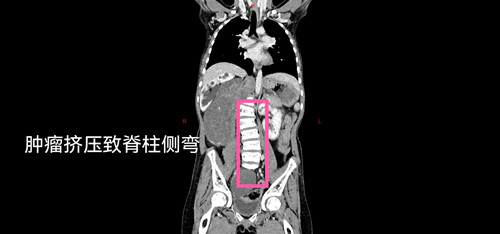

这一等,就是十年。随着年岁增长,瘤体也在疯狂生长,逐渐压迫她的胸腔和腹腔。近期,女孩出现了严重的呼吸困难,甚至无法直立行走。更令人揪心的是,她还患有双侧先天性马蹄内翻足和脊柱侧弯,身体的痛苦与生活的不便想想都令人心疼。当生命的空间被肿瘤一点点挤占,这个家庭几乎走到了崩溃的边缘。

抱着一线希望,家人带着女孩来到了山西省儿童医院普外科。入院后,完善各项检查,结果比预想的更为复杂:初步诊断为节细胞神经母细胞瘤,且已伴有腹膜后广泛转移和盆腔转移。影像学显示,主肿瘤与腹主动脉、下腔静脉紧密粘连,右侧肾动脉甚至穿行于瘤体之中,而盆腔的转移灶与主瘤体不相连。这意味着,手术将如同在血管的“丛林中排雷”,稍有不慎,后果不堪设想。